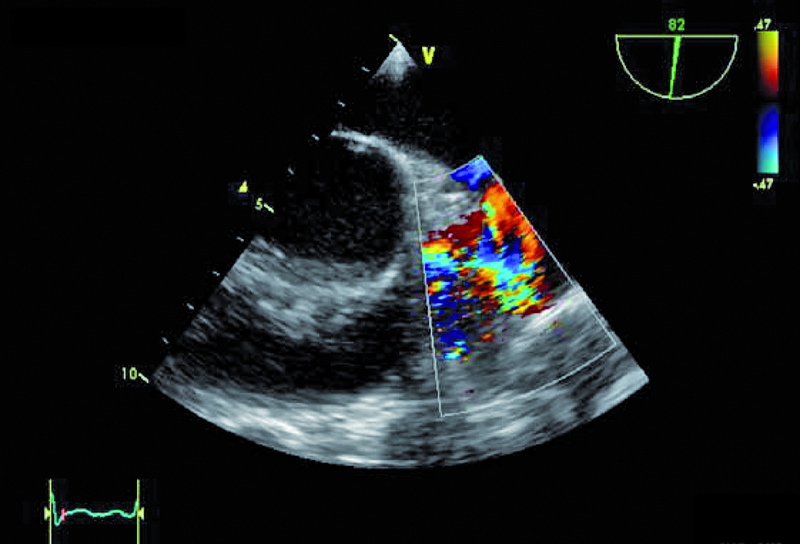

W badaniu echokardiograficznym zwrócono uwagę na powiększenie jamy lewej komory z nieznacznie upośledzoną kurczliwością mięśnia (ryc. 1). Stwierdzono także trójpłatkową zastawkę aortalną (ryc. 2) ze śladową niedomykalnością oraz małą niedomykalność mitralną. Te nieprawidłowości nie mogły tłumaczyć szmeru ciągłego w badaniu fizykalnym ani też nieznacznie powiększonej sylwetki serca. Przyczyną szmeru ciągłego jest najczęściej przetrwały przewód tętniczy Botalla, łączący aortę i pień płucny. Połączenia takiego jednak w miejscu typowym nie znaleziono. Rejestrowano u chorego prawidłową średnicę pnia płucnego (ryc. 3) oraz nieznacznie przyspieszoną prędkość wypływu płucnego (ryc. 4). Szmer ciągły nakazywał poszukiwać innych rzadkich połączeń między dużymi naczyniami. Jedną z nich jest okienko aortalno-płucne, czyli tzw. fenestracja aortalno-płucna, i tę wadę właśnie rozpoznano u chorego.

Okienko powstaje wskutek nieprawidłowego podziału embriologicznego przegrody dzielącej aortę wstępującą oraz pień płucny. Lokalizacja okienka w obrębie aorty wstępującej może być różna, zależnie od tego, która część wspólnej przegrody ulega w toku rozwoju embriologicznego uszkodzeniu – proksymalna czy dystalna w stosunku do zastawek półksiężycowatych. Do rozpoznania wady wystarczy zwykle badanie echokardiograficzne. Na poziomie zastawek powinno się rejestrować dwa niezależne pierścienie zastawek półksiężycowatych. Istnienie okienka może zwykle sugerować brak echa w ścianie między dużymi tętnicami. W tym jednak przypadku takiej cechy nie stwierdzono. Na możliwość okienka wskazywała turbulencja w badaniu kolorowego doplera w pobliżu pierścieni zastawki aortalnej i płucnej (ryc. 5, 6). W badaniu techniką kolorowego doplera rejestruje się przepływ o dużej prędkości, czasami wyraźnie ze strony lewej ku prawej lub przepływ dwukierunkowy. W różnicowaniu trzeba brać jednak pod uwagę inne nieprawidłowości, jak odejście prawej tętnicy płucnej od aorty wstępującej. Dawniej okienko aortalno-płucne operowano za pomocą łaty z dakronu bądź osierdziowej lub przy niewielkiej komunikacji za pomocą szwu. Obecnie, jeśli nie stwierdza się innych współistniejących nieprawidłowości, bierze się pod uwagę zamknięcie okienka za pomocą okludera i do tego rodzaju zabiegu chory został zakwalifikowany. Średnica okienka (4,5 mm) została ustalona w badaniu tomografii komputerowej.